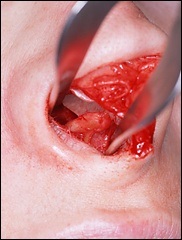

Mielőtt nagyobb acanthion. Ez az, amit úgy néz ki, a művelet során. Az ábrán a jobb ez sárga színű. Acanthion columella található, közvetlenül alatta, ahol a felső ajak határos az alapja az orrát.

Része a gerinc, amelyeket el kell távolítani jelzi a kék vonalon. Removal végezzük vésővel.

A felső és az alsó képen látható két legkiemelkedőbb nazális gerinc, a jobb kilátás bővítették segítségével horgokat.